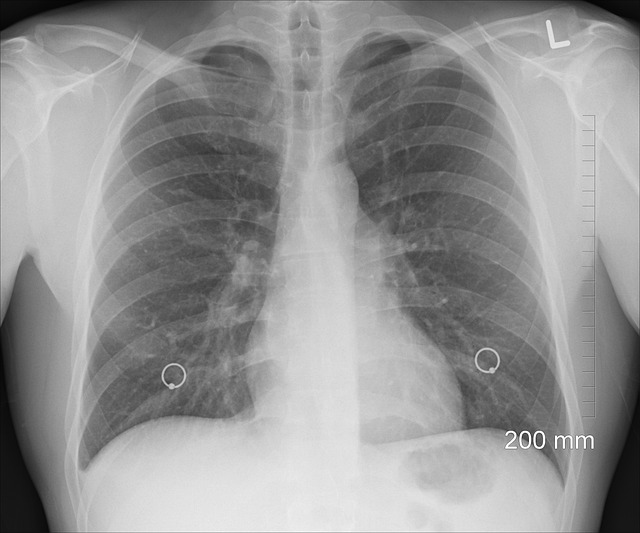

정확한 진단은 효과적인 결핵 치료의 초석입니다. 결핵 진단에는 결핵 피부 검사, 인터페론 감마 방출 검사(IGRA), 흉부 X선 등 다양한 검사가 사용됩니다. 객담 배양 검사와 핵산 증폭 검사는 활성 결핵을 확인하고 약물에 내성이 있는 균주를 확인하는 데 도움이 됩니다.